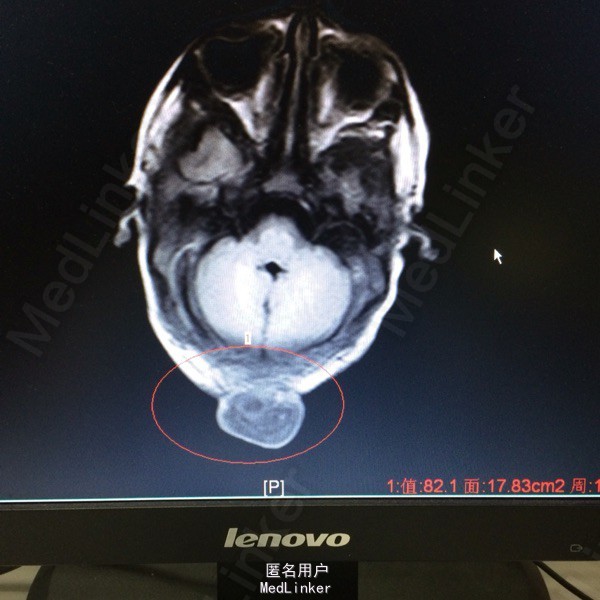

主诉:发现枕部包块1月余 病史:患儿2月大,第3胎第3产,经剖宫产,查体发现枕后部有一圆形肿物突出,约等3*3大小,透光实验阳性,质软。

查体:神志清醒,枕后部可见一圆形肿物突出,约3*3cm大小。质软,表面无溃疡等 辅助检查:胸片提示新生儿羊水吸入综合症,头颅MR提示局部脑脊膜膨出

诊断:后枕部脑脊膜膨出 处理:行脑脊膜膨出修补术,病理提示符合脑脊膜膨出